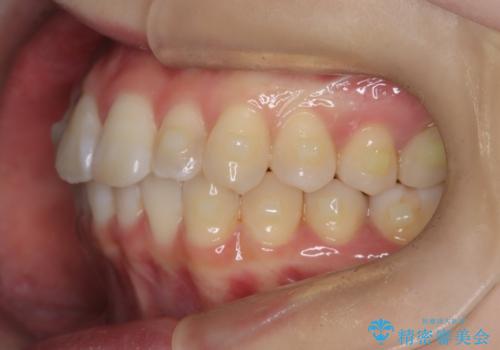

前歯のガタつきをマウスピース矯正で改善

- 前歯のガタツキが気になると来院されました。

奥歯の噛み合わせは綺麗に噛んでいたため、前歯の叢生(でこぼこ)に集中して治療するように計画しました。